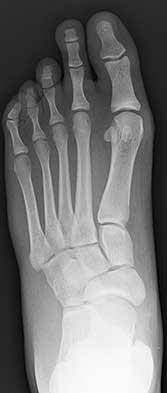

Figures 9a and 9b are the radiographs of a 19-year-old woman with a painful juvenile bunion. The pathologic findings associated with this deformity

The radiographs show a hallux valgus deformity with a laterally deviated distal metatarsal articular surface, a large intermetatarsal angle with medial deviation at the first metatarsocuneiform joint, an elongated medial collateral ligament, and a contracted lateral collateral ligament. There is no distal 1-2 transverse intermetatarsal ligament. The distal transverse ligament in the first interspace extends from the second metatarsal to the lateral (fibular) sesamoid, remains intact, and keeps the sesamoids in a lateral position as the first metatarsal head migrates medially.